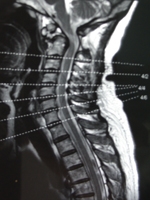

臨床表現無特異性診斷主要依據X線平片,包括正、側位,左、右斜位及伸屈動力位片。對有疑問的病例應行斷層攝片,從而更清楚地顯示病變部位。CT和MRI檢查對診斷本病僅提供參考但有助於鑑別與發現其他疾患。本病的X線片特點為(圖1):

值得注意的是,在CT掃描切層上,頸椎椎弓裂與腰椎峽部裂表現不盡相同,其主要表現為關節突與椎體相連部位連續性中斷,斷端光滑,關節突與椎體的夾角也不同。